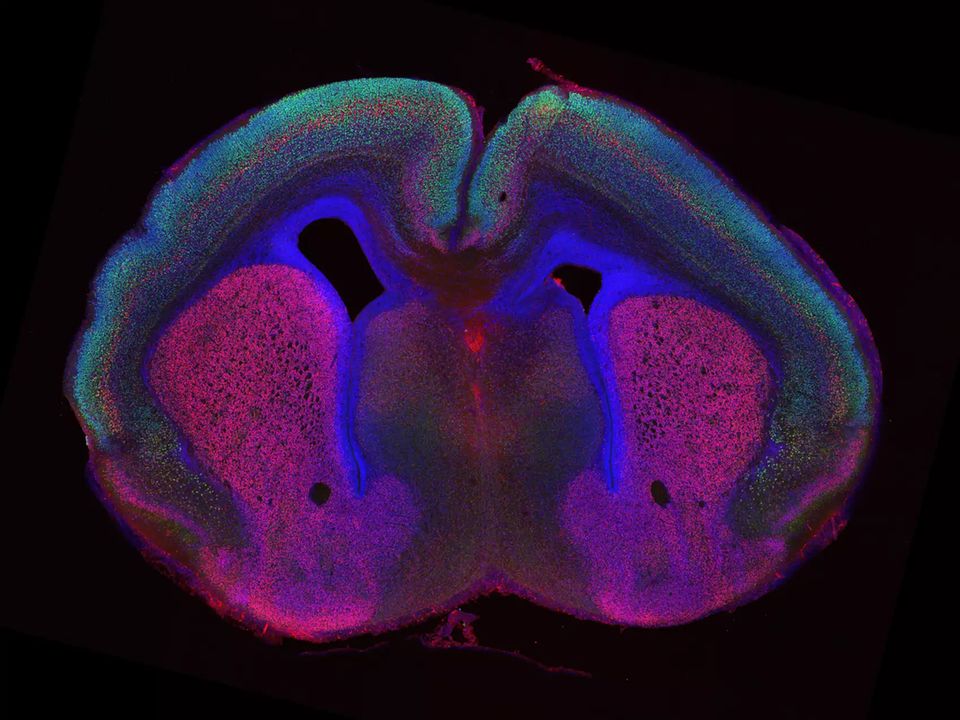

Doch wie sich unsere Großhirnrinde faltet, ist ein Rätsel, das bisher nur in Teilen gelöst ist. Um der Antwort ein Stück näher zu kommen, haben Seung Hee Chun, Rüdiger Klein und ihr Team sich das Gehirn von Mäusen angeschaut: Dabei haben sie drei Gene identifiziert, die maßgeblich für die Faltstruktur des Gehirns verantwortlich sind.

Wie viele andere Lebewesen hat auch die Maus eine glatte Hirnoberfläche. Wird bei der Maus das Gen für das Protein Cep83 ausgeschaltet, bilden sich plötzlich Furchen (fachsprachlich Sulci) und Erhebungen (Gyri). Ohne Cep83 vermehren sich die Vorläuferzellen der Neuronen während der Hirnentwicklung, sodass der Kortex stärker wächst – es entsteht ein Zellüberschuss. Die Forschenden beobachteten gleichzeitig, dass der Kortex sich mit dem Wachstum faltet. So entstanden die Furchen und Erhebungen vermutlich auch vor tausenden Jahren, als der Kortex des Menschen anwuchs, die Schädeldecke aber nicht mit dem Wachstum Schritt hielt.

Die stärksten Veränderungen der Hirnanatomie entstanden im Zusammenspiel von deaktivierten Flrt1/3 Genen und stillgelegten Genen, die Cep83 und Fgf10 kodieren. Hier traten bei fast allen genveränderten Tieren Falten im Kortex auf. Noch unklar ist, ob die Furchen, die die Forschenden mit der Genmanipulation erzeugen konnten, auch eine sinnvolle Funktion erfüllen.